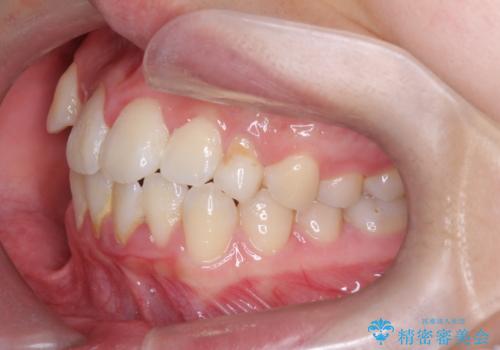

【埋伏歯】犬歯の牽引を行った矯正歯科治療

- 八重歯を主訴に来院されました。

左側犬歯が埋伏していましたが、第一小臼歯(4番目の歯)を抜歯したことでできたスペースに牽引し、右側の飛び出した八重歯を含め、歯全体を整列することができ患者様も満足していただきました。